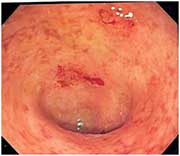

ΕΛΚΩΔΗΣ ΚΟΛΙΤΙΔΑ

Νικόλαος Αθανασόπουλος, Γαστρεντερολόγος-Ηπατολόγος-Επεμβατικός Ενδοσκόπος

Επιμελητής Γαστρεντερολογικής Κλινικής, Γενικής Κλινικής Πειραιώς «Ιπποκράτης»

Η ελκώδης κολίτιδα (ΕΚ) είναι μια χρόνια ιδιοπαθής φλεγμονώδης νόσος του γαστρεντερικού συστήματος, που προσβάλλει πρωτογενώς το παχύ έντερο και αποτελεί μέρος μιας ευρύτερης κατηγορίας ασθενειών που καλείται Ιδιοπαθής Φλεγμονώδης Εντερική Νόσος (ΙΦΕΝ).

ΤΙ ΕΙΝΑΙ Η ΕΛΚΩΔΗΣ ΚΟΛΙΤΙΔΑ;

Βασιλική Αρβανίτη, Γαστρεντερολόγος-Ηπατολόγος-Ενδοσκόπος, υπ. Διδάκτωρ Πανεπιστημίου Πατρών, Μετεκπαιδευθείσα στο Λονδίνο

Επιμελήτρια Γαστρεντερολογικής Κλινικής, Γενικής Κλινικής Πειραιώς «Ιπποκράτης»

Η ελκώδης κολίτιδα είναι μια χρόνια φλεγμονή του παχέος εντέρου. Χρόνια φλεγμονή σημαίνει πως ο ασθενής μπορεί να έχει συμπτώματα για μεγάλο χρονικό διάστημα και ότι η θεραπεία του διαρκεί για μήνες ή και χρόνια.